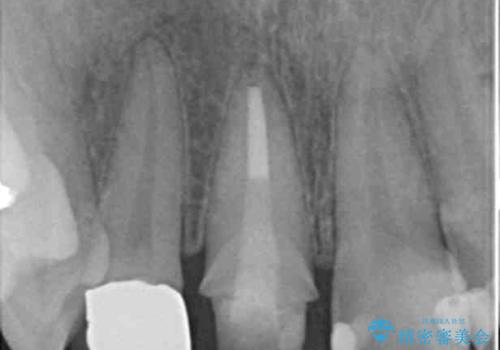

右上1番は、根の治療のやり直しをしています。

- 63.8万円(右上4~左上2:emaxクラウン 7万円x6本、仮歯 1万円x6本、歯周外科手術 15万円、右上1:精密根管再治療 9万円およびファイバーコア2万円)費用は治療当時の料金となります